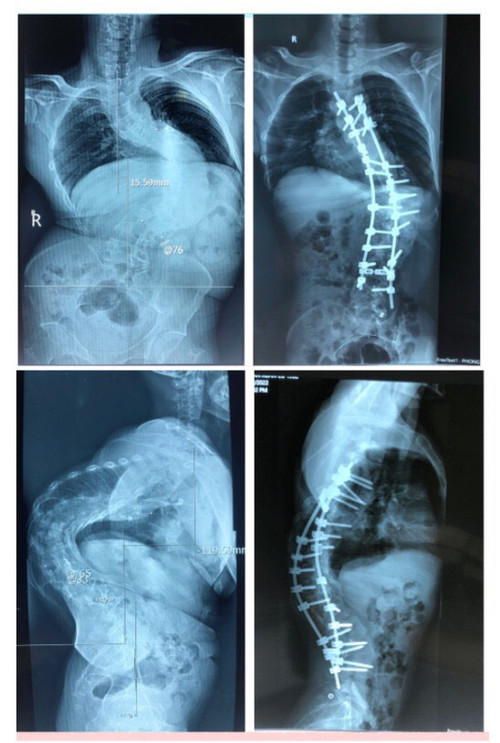

Qua các hình ảnh X-quang, tình trạng thực tế của bệnh nhân, các bác sĩ xác định đây là một ca bệnh đặc biệt khó, góc vẹo rất lớn T6L3 khoảng 126 độ, hơn nữa ca bệnh này càng khó khăn hơn là kèm theo gù cũng rất lớn hơn 100 độ.

| Phim chụp X-quang trước và sau phẫu thuật nắn chỉnh gù. |

Trước ca bệnh này, nghiên cứu y văn và những kinh nghiệm trước đây, các bác sĩ đã quyết tâm phẫu thuật cho bệnh nhân, với 2 thì mổ: Thì thứ nhất đi lối trước, cắt xương sườn, vén phổi, cắt tối đa được 4 đĩa đệm để làm lỏng cột sống, sau đó lắp khung Halo kéo dãn trên giường nghiêng 30 độ, trong thời gian 3 tuần, với cân nặng tăng dần đến lúc đạt mức tối đa là 50% cân nặng của bệnh nhân. Thì thứ 2, đi lối sau, bắt vít nắn chỉnh vẹo.

Cũng bởi vì ca bệnh gù rất lớn, nên Tiến sĩ, bác sĩ Phan Trọng Hậu – Chủ nhiệm Khoa Chấn thương chỉnh hình cột sống cũng là bác sĩ trực tiếp mổ cho anh A đã quyết định cắt V xương ở 3 mức để nắn chỉnh.

Sau mổ, hình thể người bệnh đã gần như bình thường, chiều cao tăng thêm vài cm. Người bệnh đã cảm thấy thở dễ hơn, đi lại cũng ổn hơn, và quan trọng nhất là đã tự tin hơn rất nhiều trong cuộc sống.